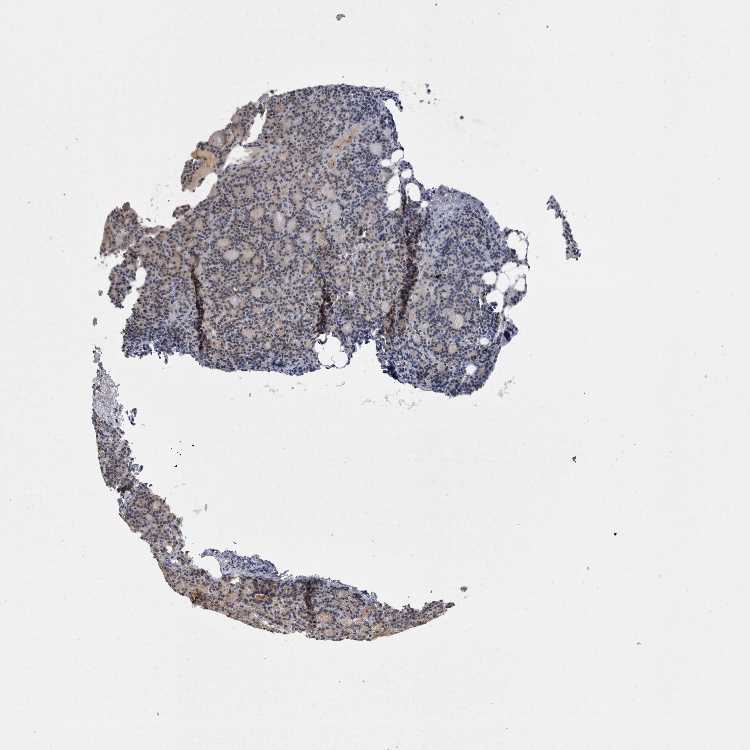

PARATHYROID GLAND - Antibody stainingi

Antibody staining in the annotated cell types in the current human tissue is reported as not detected, low, medium, or high, based on conventional immunohistochemistry profiling in selected tissues. This score is based on the combination of the staining intensity and fraction of stained cells.

Each image is clickable and will lead to virtual microscopy that enables deeper exploration of all samples and also displays staining intensity scores, fraction scores and subcellular localization as well as patient and tissue information for each sample.

Antibody HPA026687

Glandular cells Low